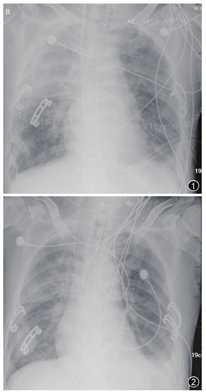

患者何某,男,68岁,因"反复咳嗽咳痰气促10年,加重1个月余",于2015年3月2日带经口气管插管接呼吸机辅助通气转入我科。转入诊断:(1)慢性阻塞性肺疾病(chronic obstructive pulmonary disease,COPD)急性加重期;(2)Ⅱ型呼吸衰竭 ;(3)双侧肺炎。入科后根据痰细菌培养(铜绿假单胞菌),予头胞哌酮钠舒巴坦钠治疗。5 d后患者病情改善,拔除气管插管后予无创通气辅助。无创通气5 d后因患者感染加重、呼吸衰竭,再次予插管行有创通气及继续抗感染等治疗。经多学科讨论,根据病史、临床表现,胸部CT等确定患者为终末期COPD,符合肺移植入选标准。肺功能(6个月前外院行肺功能检查,因患者气促明显无法完成肺功能检查)。于2015年3月24日行"蚌式切口双肺移植术"。术中见双肺呈灰黑色并过度膨胀,内部和表面充满散在肺大泡,全肺弹性和顺应性明显降低,局部有结节状表现,右中下胸膜粘连严重。受体切除肺组织病理:慢性支气管炎、肺大泡性肺气肿伴机化性肺炎。手术先左侧后右侧,供肺来源:公民逝世后器官捐献(donation after cardiac death,DCD)。术后体温38.2℃,右上肺纤支镜下可吸出大量脓血性分泌物,胸片示双肺渗出影,右上肺明显(图1),考虑与肺损伤及术后肺部感染进展有关。术后予美洛培南、万古霉素、卡泊芬净、更昔洛韦抗感染治疗,予甲泼尼龙、他克莫司、霉酚酸酯三联抗排斥治疗。术后第3天因病原学回报患者供体肺组织培养结果为耐甲氧西林金黄色葡萄球菌(meticillin-resistant Staphylococcus aureus,MRSA),表皮葡萄球菌、发酵乳杆菌,受体残肺组织培养为多耐药铜绿假单胞菌、粪肠球菌,予停万古霉素改用利奈唑胺抗球菌感染。术后第7天出现寒战发热,体温最高达40℃,血压100/50 mmHg[去甲肾上腺素0.6 μg/(kg•min),1 mmHg=0.133 kPa],诊断考虑:败血症、感染性休克,行血培养。血培养回报革兰阴性杆菌(鲍曼不动杆菌),使用美罗培南(6.0持续静脉输注)联合使用头胞哌酮钠舒巴坦钠(3.0静脉滴注q8 h)抗感染治疗,静脉免疫球蛋白治疗5d[剂量0.4 g/(kg•d)]及液体复苏、血管活性药物等抗休克治疗;同时,停用他克莫司、霉酚酸酯,予静脉甲基强的松龙(40 mg/d)抗排斥治疗。术后第17天患者体温逐渐下降至正常,循环稳定。根据病原学降级抗生素为头胞哌酮钠舒巴坦钠,加回他克莫司和霉酚酸酯抗排斥治疗(图2)。术后第22天拔出气管插管,予无创通气过度后转普通病房。术后3个月出院回家,胸部CT检查见肺部手术前后的影像学变化(图3,图4,图5,图6,图7,图8,图9,图10,图11),目前一般情况良好。